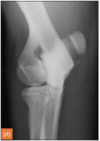

Q

Monteggia fractures